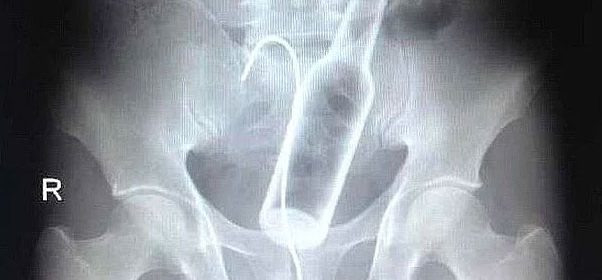

Röntgen filmlerinden "akıl almaz şeyler

Hastane koridorlarına düşenler bilir… Doktora görün, tahlilleri yaptır, röntgenleri çektir falan filan derken sayılmadan ömür gider. Gelin ki bu sefer ilginç şeyler çıkmış ki görün ağzımız açık kaldı…